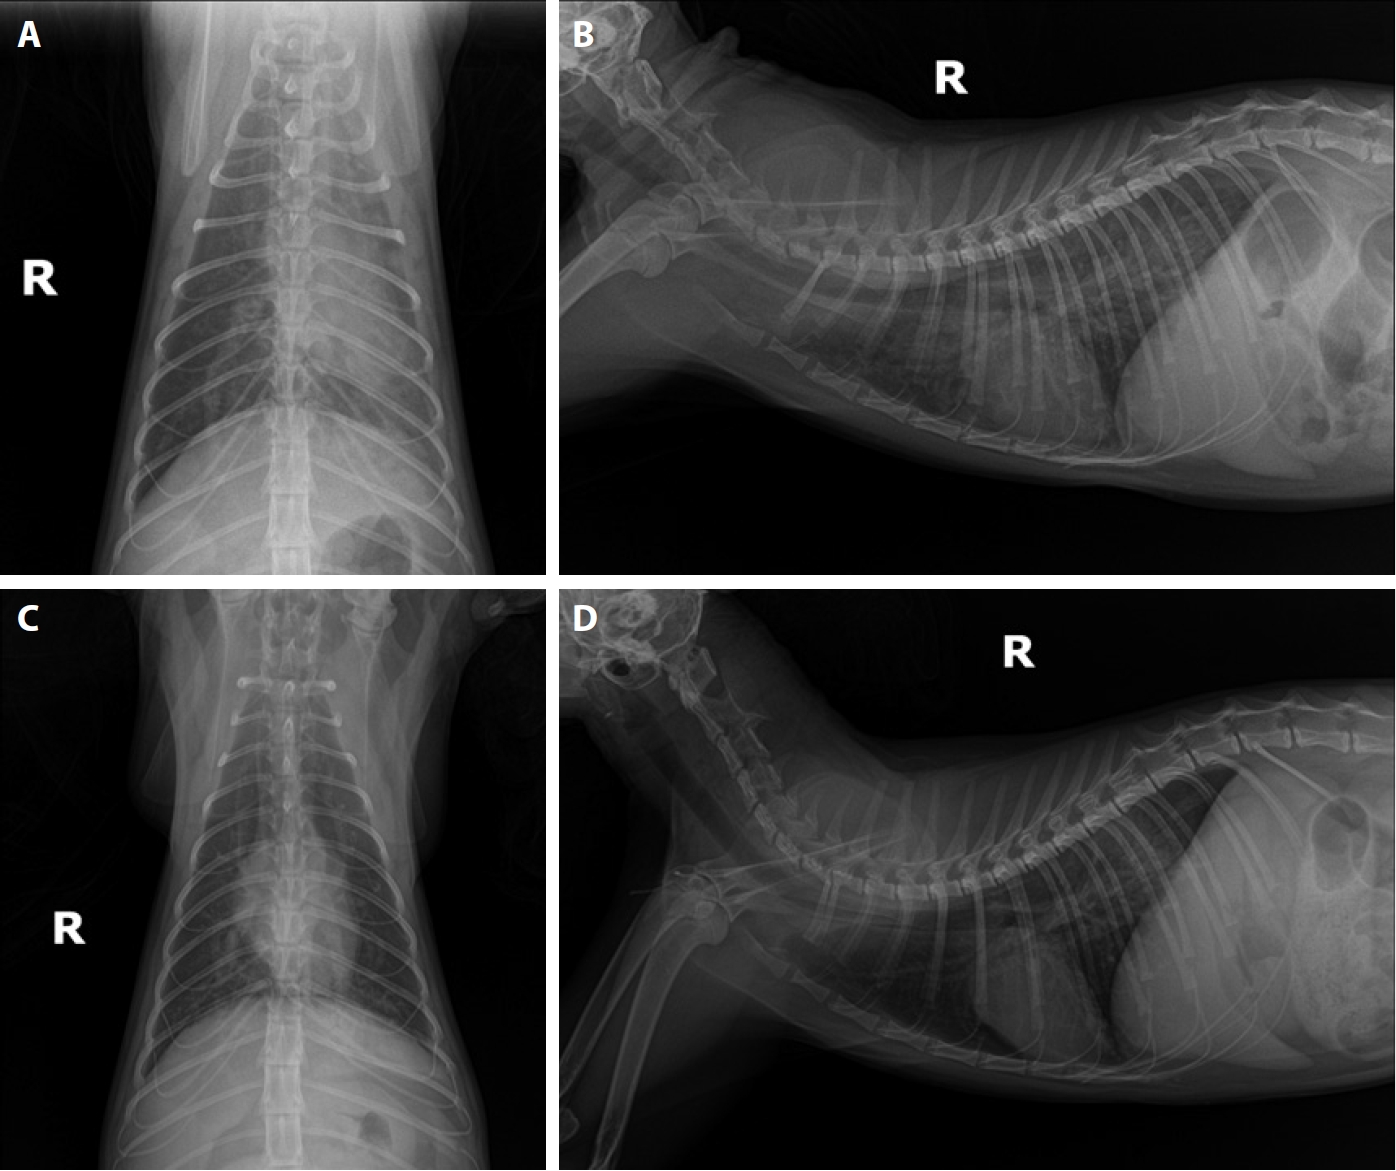

Feline heartworm (Dirofilaria immitis) infection in stray cats in Ulsan, Korea

Jihyun Kim, Miryeng Kim, Seungjin Lee, Youngmin Yun

Parasites Hosts Dis 2026;64(1):92-97.

Published online January 22, 2026

DOI: https://doi.org/10.3347/PHD.25076

Feline heartworm (Dirofilaria immitis) infection is an uncommon but clinically significant disease in Korea. A retrospective review of electronic medical records from a secondary referral animal hospital in Ulsan, Korea, identified 2 antigen-positive (1.5%) cases among 130 stray cats tested between 2019 and 2023, while no infections were detected in 298 client-owned cats. As antigen testing may yield false-negative results in cats with male-only infections, the true prevalence is likely underestimated. This report describes the clinical and echocardiographic findings of 2 infected stray cats. Case 1 involved successful long-term management of heartworm-associated respiratory disease, with the cat remaining healthy for 4 years following diagnosis. Case 2 demonstrated persistent evidence of adult heartworms and sudden death after an asymptomatic period of 1 year. Echocardiography in Case 2 revealed multiple hyperechoic double lines within the pulmonary arteries, consistent with intraluminal adult worms. These cases illustrate the diagnostic challenges and variable clinical outcomes of feline heartworm infection, emphasizing the need for increased awareness in Korea.